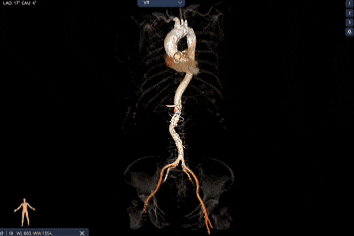

外周双侧入路无明显迂曲、直径可容纳20F大鞘通过,双侧中分叉,穿刺需注意。主动脉弓角弓距可,髂总动脉及分支多处钙化,瓷化升主动脉,钙化由升主动脉蔓延至主动脉弓侧壁及弓顶弓底部,有一定卒中和夹层风险。

该病例术前传导阻滞,室间隔膜部短,有一定永久起搏器植入风险;瓷化升主动脉,高夹层与卒中风险,在既往研究中,瓷化升主动脉患者缺血性卒中发生率为9.4%,普通患者为2.1%,围手术期缺血性中风的风险增加了4倍以上,瓷化升主动脉患者即使未行手术,其自然病程中夹层风险也可能是普通人群的 2-3倍。

经过庄晓东教授团队分析,拟右股动脉作为主入路,使用可调弯长鞘建立通道,使用18mm球囊预扩,选择AV23号Prostyle A®瓣膜进行释放。

Step 2.建立大鞘通路:大鞘通过升主、边进入边加弯,避免剐蹭弓部斑块